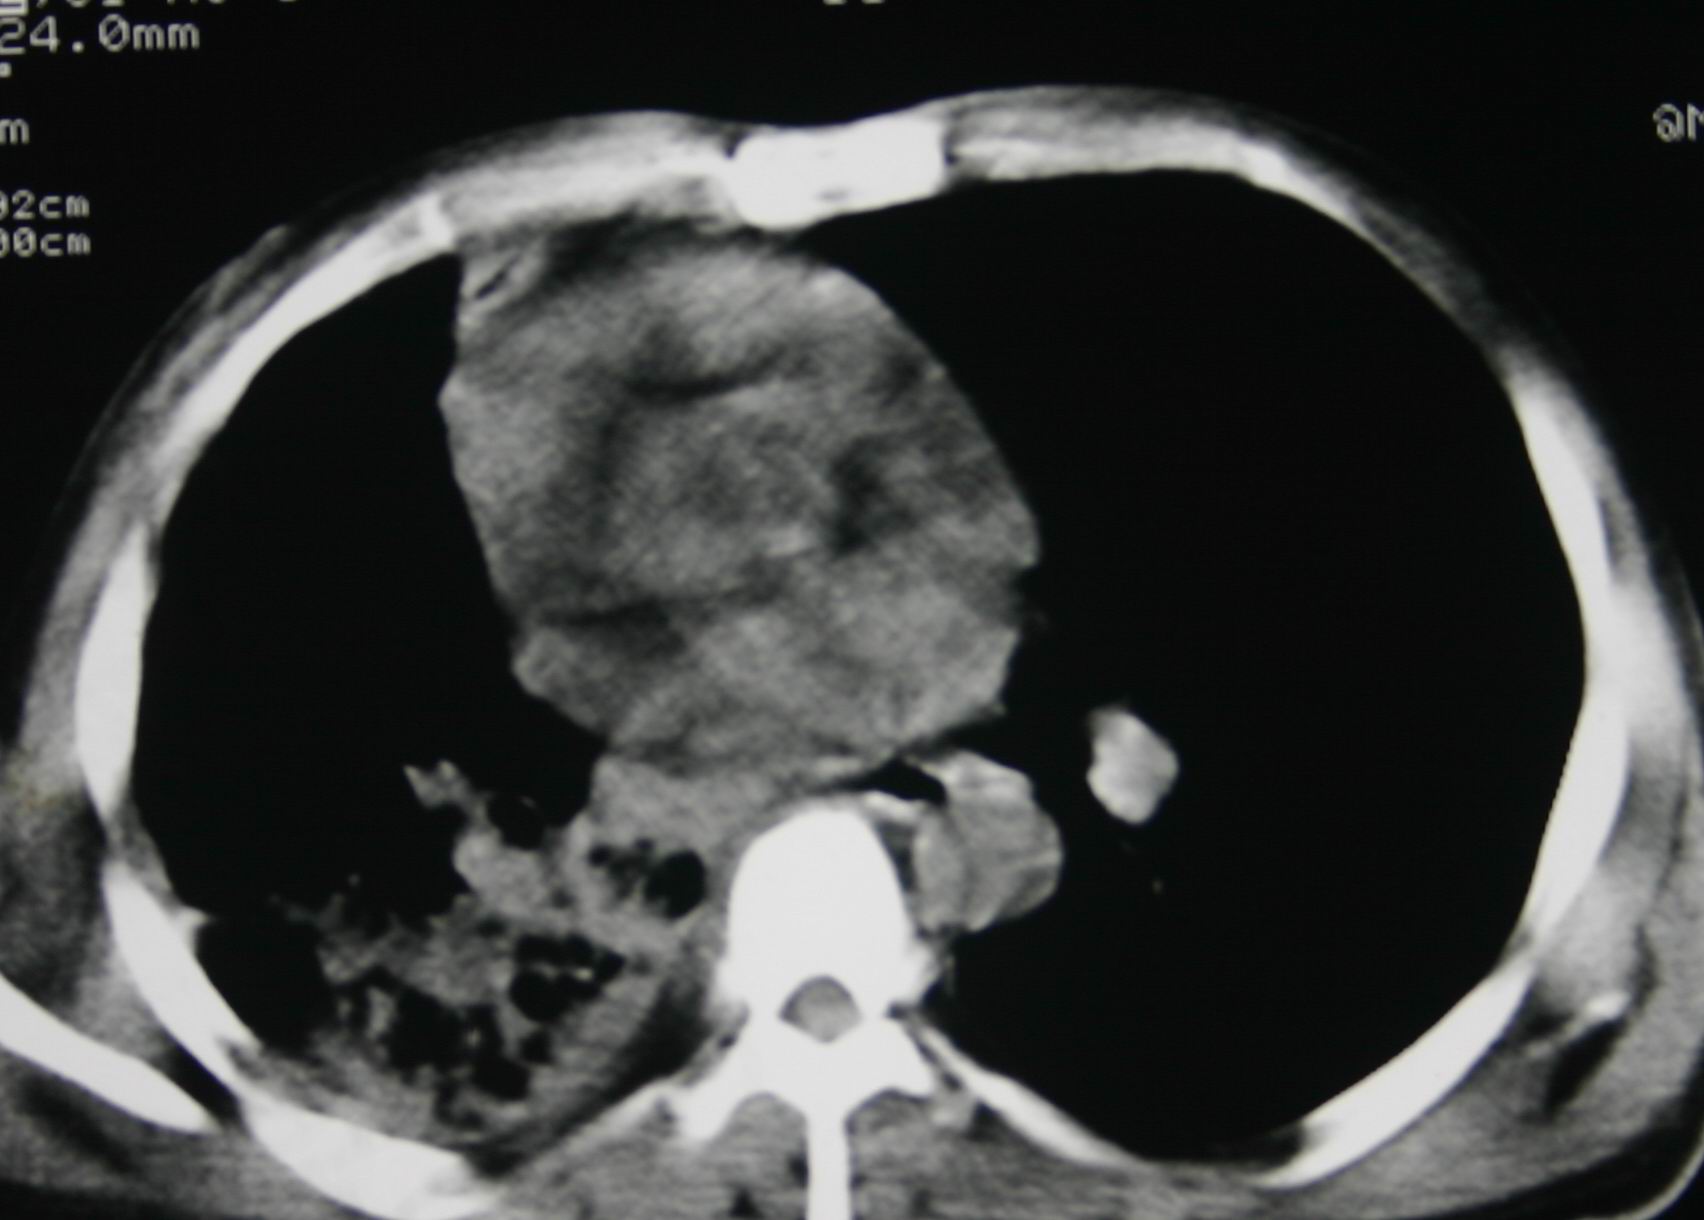

患者,男 ,48岁,反复咯血三个月,每三到五天咯一次,每次约200ml,鲜红色,无明显咳痰,咳嗽明显,无明显胸痛,无发烧,初期以抗感染、止血治疗,第一次ct报占位,支气管镜未见明显ca细,肺ca标志物、tb抗体均阴性,经过垂体后叶素、酚妥拉明、头胞他定、洛美沙星、立止血等治疗后,现病人一般情况好,停止咯血10天,咳嗽减少,咳黄脓痰,每日一次,每次30ml。现复查ct

右肺膨胀不全,纵隔右侧移位。肺内有感染,胸腔有积液。建议老片对比。

1)考虑右肺继发性肺结核合并感染。2)右侧胸腔积液+胸膜增厚。

感染性病变,结核可能性大,伴结核性胸膜炎。